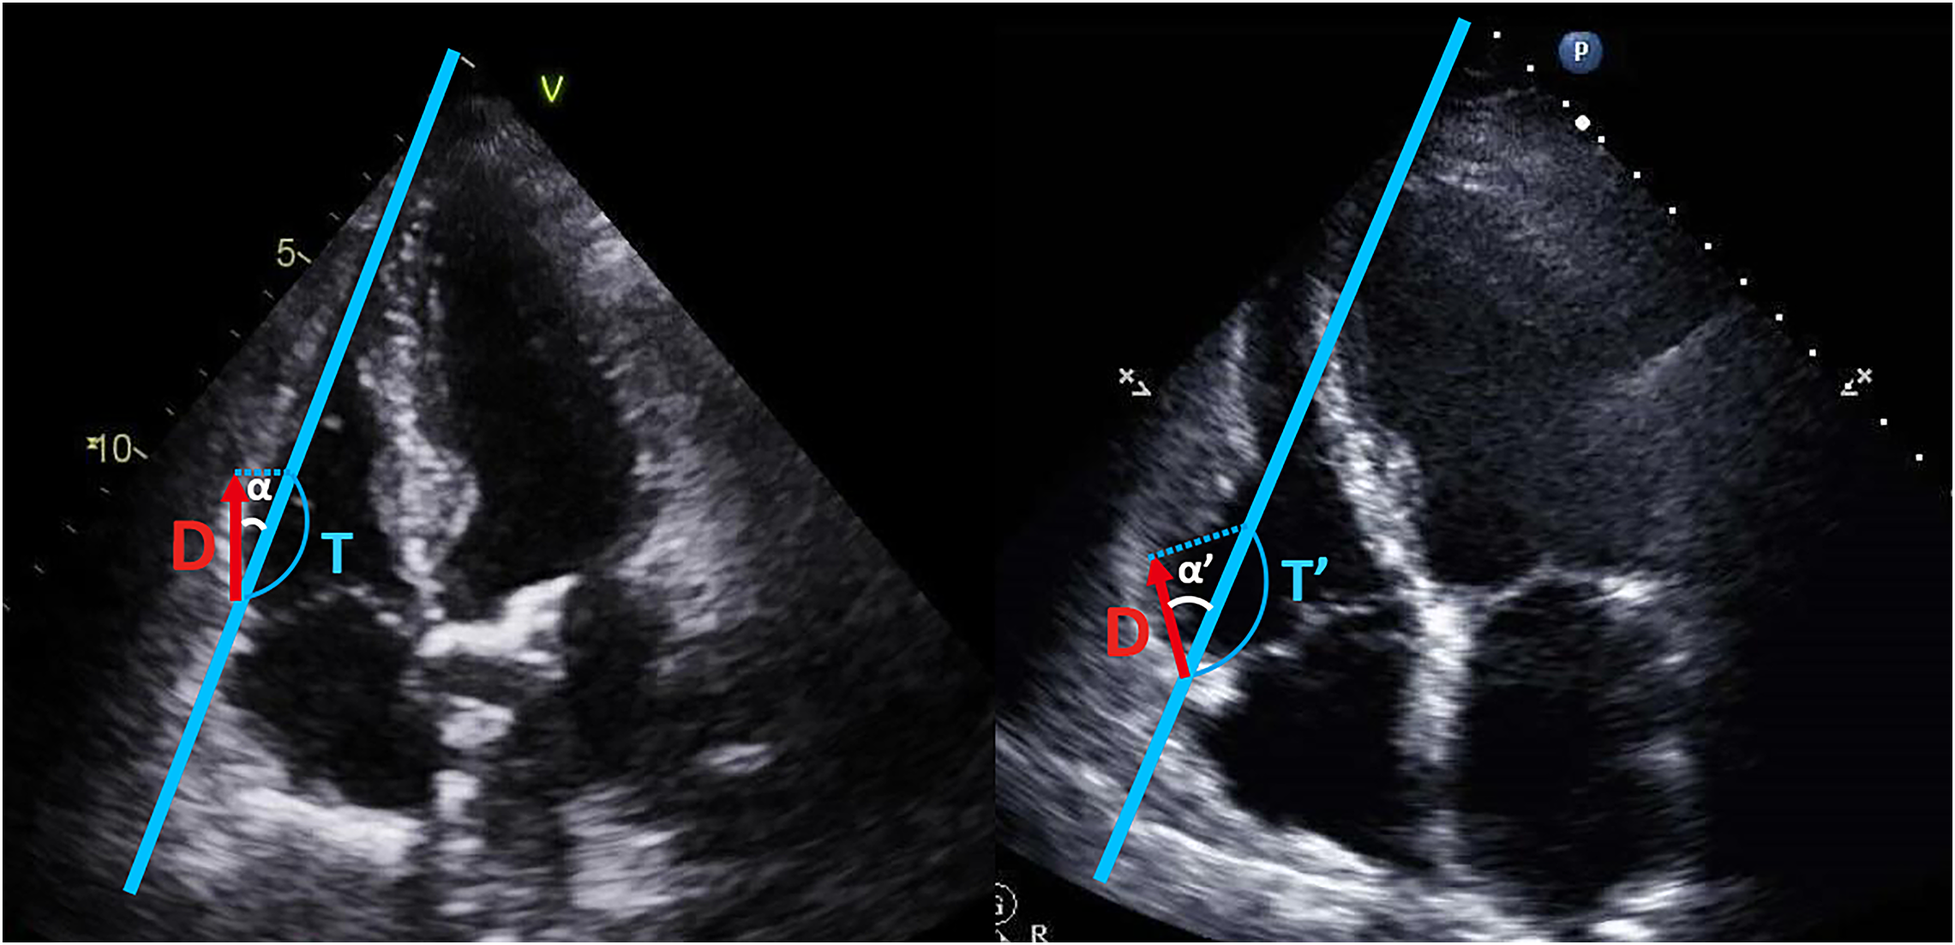

Regarding TAPSE and RV S', they have one additional significant limitation, angle dependency. Since two of them are Doppler techniques, these can be underestimated depending on the cosine of the angle between the ultrasound beam and the true tricuspid annulus motion, as shown by the formulas in Figure 4 (20).

Figure 4

Angle dependency of TAPSE and RV S’. TAPSE and RV S’ are angle-dependent indices. The measured values (T, T’) for TAPSE and RV S’, depend on the cosine of angle α and α’. As the angle α increases to the angle α’, the value can be overestimated, as shown by the formulas below:. TAPSE, tricuspid annular plane systolic excursion; RV S’, systolic tissue Doppler velocity of the tricuspid annulus; D, the actual distance of longitudinal tricuspid annulus movement; T, T’, measured value (TAPSE, RV S’); α, α’, the angle between the ultrasound beam and the longitudinal axis of tricuspid annulus motion.